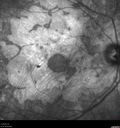

Concentric Geographic Atrophy - 76 year old man386 viewsGradual vision loss, worse at night. VA 20/40 OU.     (0 votes)

76 year old man The patient has noticed that his vision is getting worse at night. The vision loss has come on gradually. He notices that his vision in low lighting is poor and at night with oncoming headlights.

VA OD: Dcc20/40-1 NscJ7

VA OS: Dcc20/40-1 NscJ7

IOP: TP: OD:17 OS:18 Time:12:01 PM